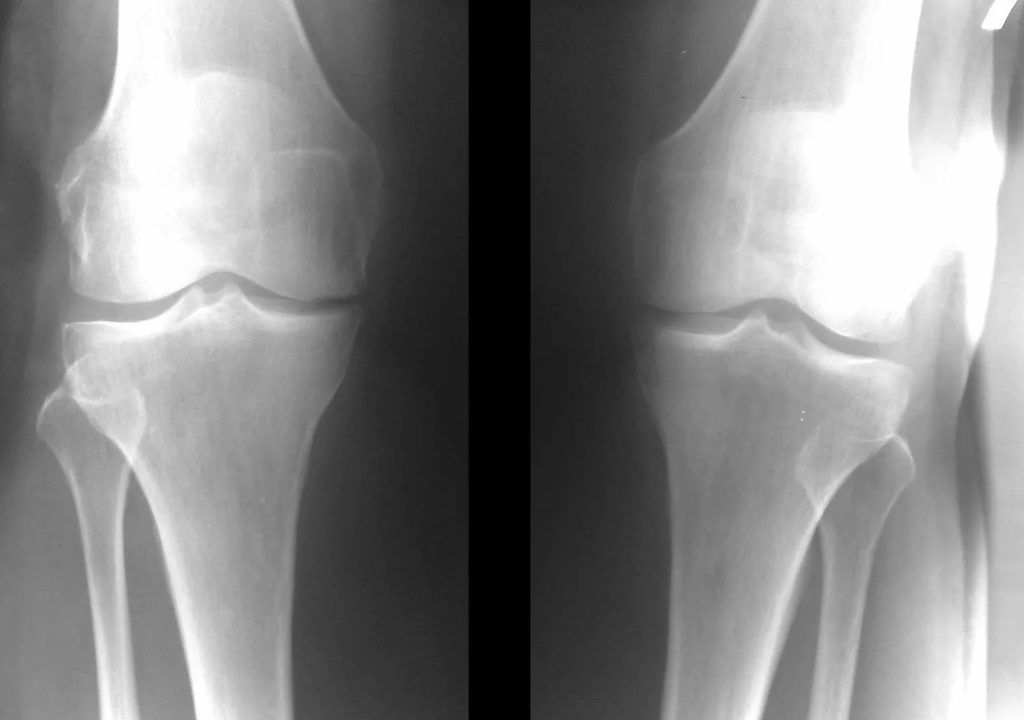

Diagnostic instrumental de l'arthrose de l'articulation du genou

Dans la grande majorité des cas, un examen et une radiographie de l'articulation du genou en deux projections (directe et latérale) suffisent. Les données cliniques et les images permettent de déterminer le stade de la maladie.

Aux premiers stades de la maladie, avec des modifications mineures du tissu osseux, un examen aux rayons X n'est pas si utile. À ce stade, la gonarthrose peut être diagnostiquée par arthroscopie. La précision de la méthode est très élevée ; Seuls son caractère invasif et son prix peuvent l’arrêter.

L'échographie ne permet pas de visualiser clairement les modifications du cartilage articulaire et des structures intra-articulaires. L'IRM vous permet de détecter les modifications des structures osseuses, cartilagineuses et des tissus mous de l'articulation, ainsi que de l'os sous-chondral avec une précision de 85 %. La scintigraphie peut être utilisée pour évaluer l'activité métabolique du tissu osseux périarticulaire.